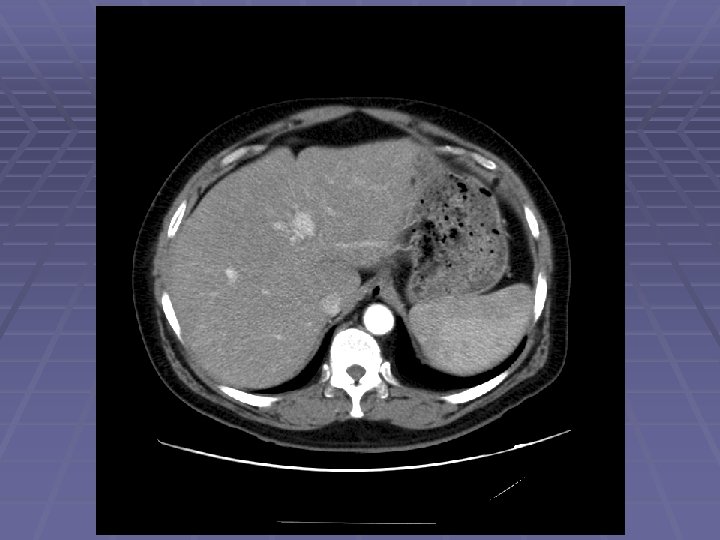

EUS Evaluation of Left Lobe of Liver